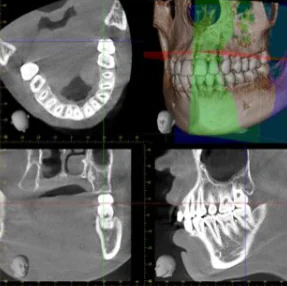

精密歯科用CTを用いた精度の高い診査診断が無料

当院では、インプラント治療の成功を確かなものとするため、患者様のお口の状態を正確に把握し、それに基づく綿密な治療プランを構築します。

そのために、必要不可欠なのがCT診断です。当院では精密歯科用CTを導入して診査診断を行なっています。インプラントを埋入する部位には目視できない神経や血管があり、それらを把握せずにインプラント治療を行うことはできません。精密歯科用CTにより顎の骨の立体的な構造や神経の位置などを高精度に把握できます。 当院ではそれらの診査診断を無料で行っているのでいつでも話をしたい旨を伝えていただければ相談させていただきます。

当院では、インプラント治療の成功を確かなものとするため、患者様のお口の状態を正確に把握し、それに基づく綿密な治療プランを構築します。

そのために、必要不可欠なのがCT診断です。当院では精密歯科用CTを導入して診査診断を行なっています。インプラントを埋入する部位には目視できない神経や血管があり、それらを把握せずにインプラント治療を行うことはできません。精密歯科用CTにより顎の骨の立体的な構造や神経の位置などを高精度に把握できます。 当院ではそれらの診査診断を無料で行っているのでいつでも話をしたい旨を伝えていただければ相談させていただきます。

最新のデジタルシミュレーションによる埋入計画

当院ではCT撮影した画像をシミュレーションソフトに取り込み、患者様の骨の状態を立体的に詳細に把握します。この情報を元に、最適なインプラントサイズ・埋め込み位置・角度・深さを細かく決定します。特に症例によっては、サージカルガイドと呼ばれるマウスピース型の器具を製作します。このガイドは、シミュレーションに基づいて決定された位置へ正確にインプラントを埋入するための専用定規のようなものです。

サージカルガイドを使用することで、手術の正確さが格段に向上し、患者様の身体への負担も大幅に軽減されます。